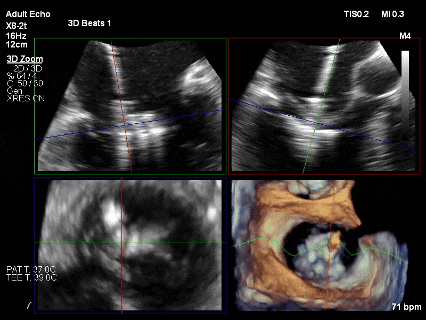

为了避免长时间TEE对食道造成损伤,术前即刻3D-TEE短时进一步明确二尖瓣病变相关解剖情况。

术前Bi-com

术前3D

3D-TEE二尖瓣相关解剖学参数:后叶长度:22-25mm,前叶长度:31-34mm;瓣环AP径:47mm,ML径:48mm;瓣口面积:约7.8cm²;脱垂宽度:30mm,最大连枷间距:14mm。

四条肺静脉均可测及收缩期反向血流

术前即刻TEE进一步明确了二尖瓣反流的机制(DMR)及反流程度(5+),重点完善了病变区域二尖瓣解剖结构的评估,预估手术难点/影响手术效果的解剖结构为冗长的二尖瓣后叶(PML约25mm),宽大的脱垂(Flail Width约30mm),超大的连枷间距(Flail gap约14mm)。